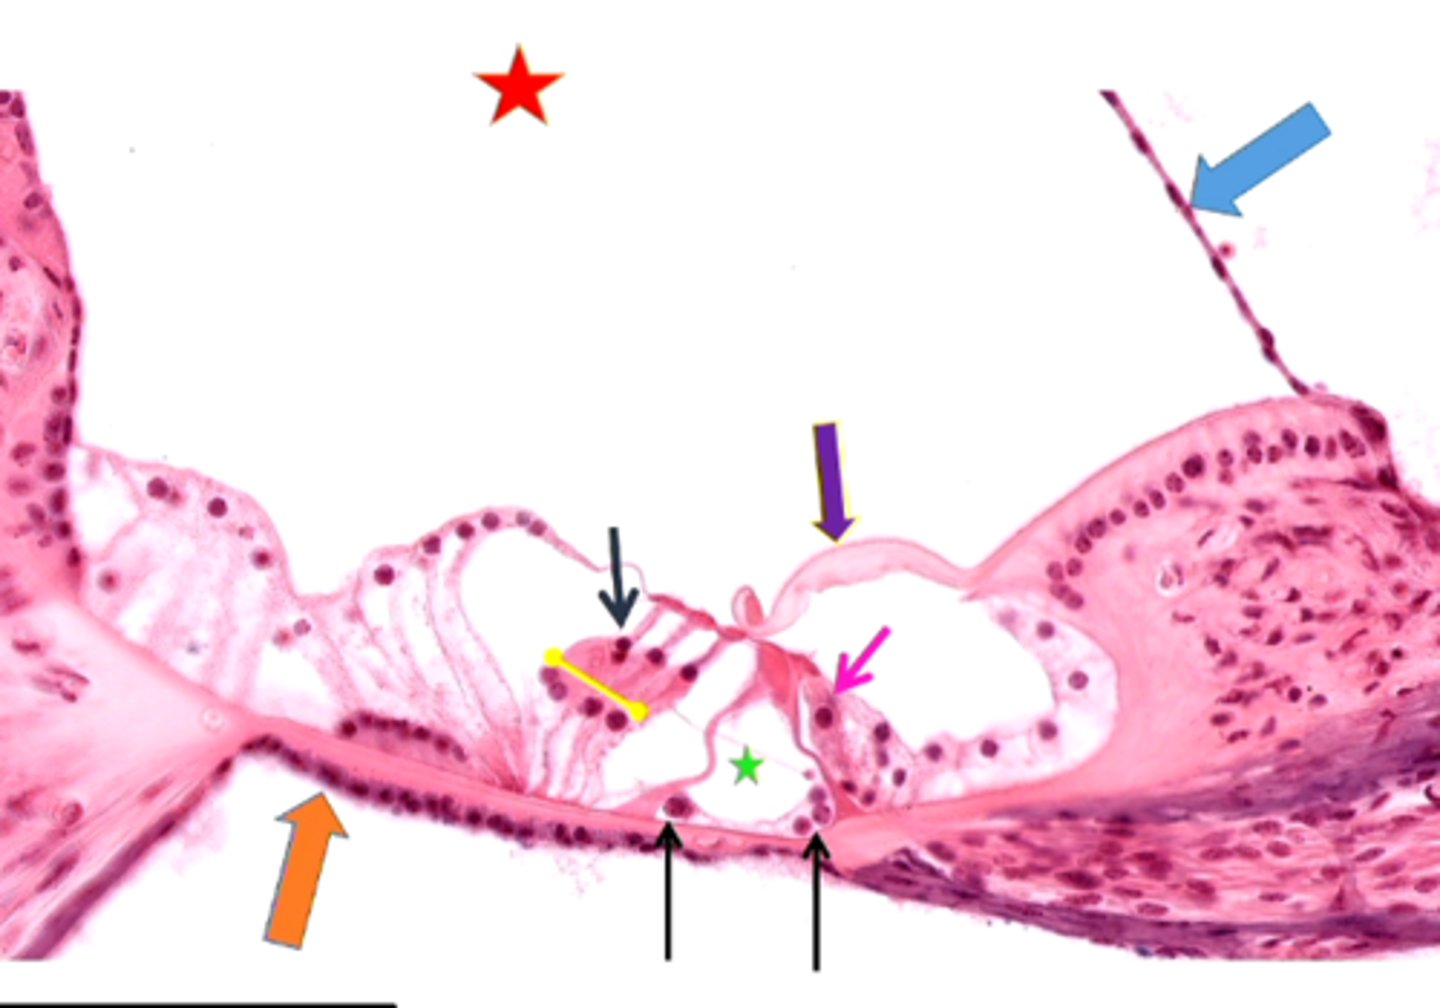

cochlea histology

scala vestibuli

contains perilymph

scala media

contains endolymph

scala tympani

vestibular membrane

organ of Corti

tissue containing the hair cells necessary for hearing

basilar membrane

hair cells

tectorial membrane